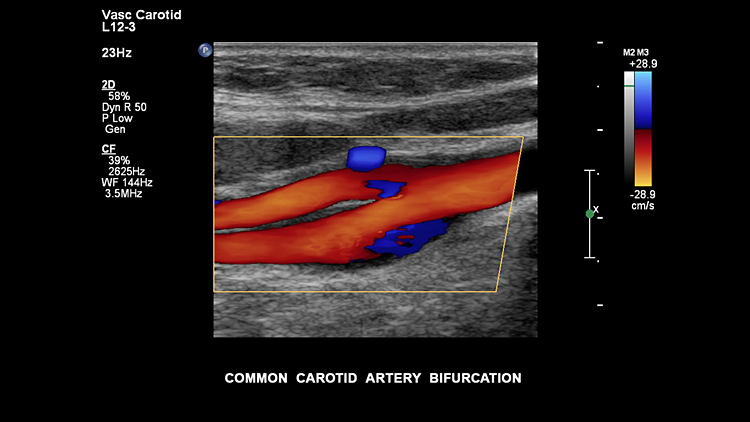

Общая сонная артерия, L12-3

Бифуркация общей сонной артерии, L12-3